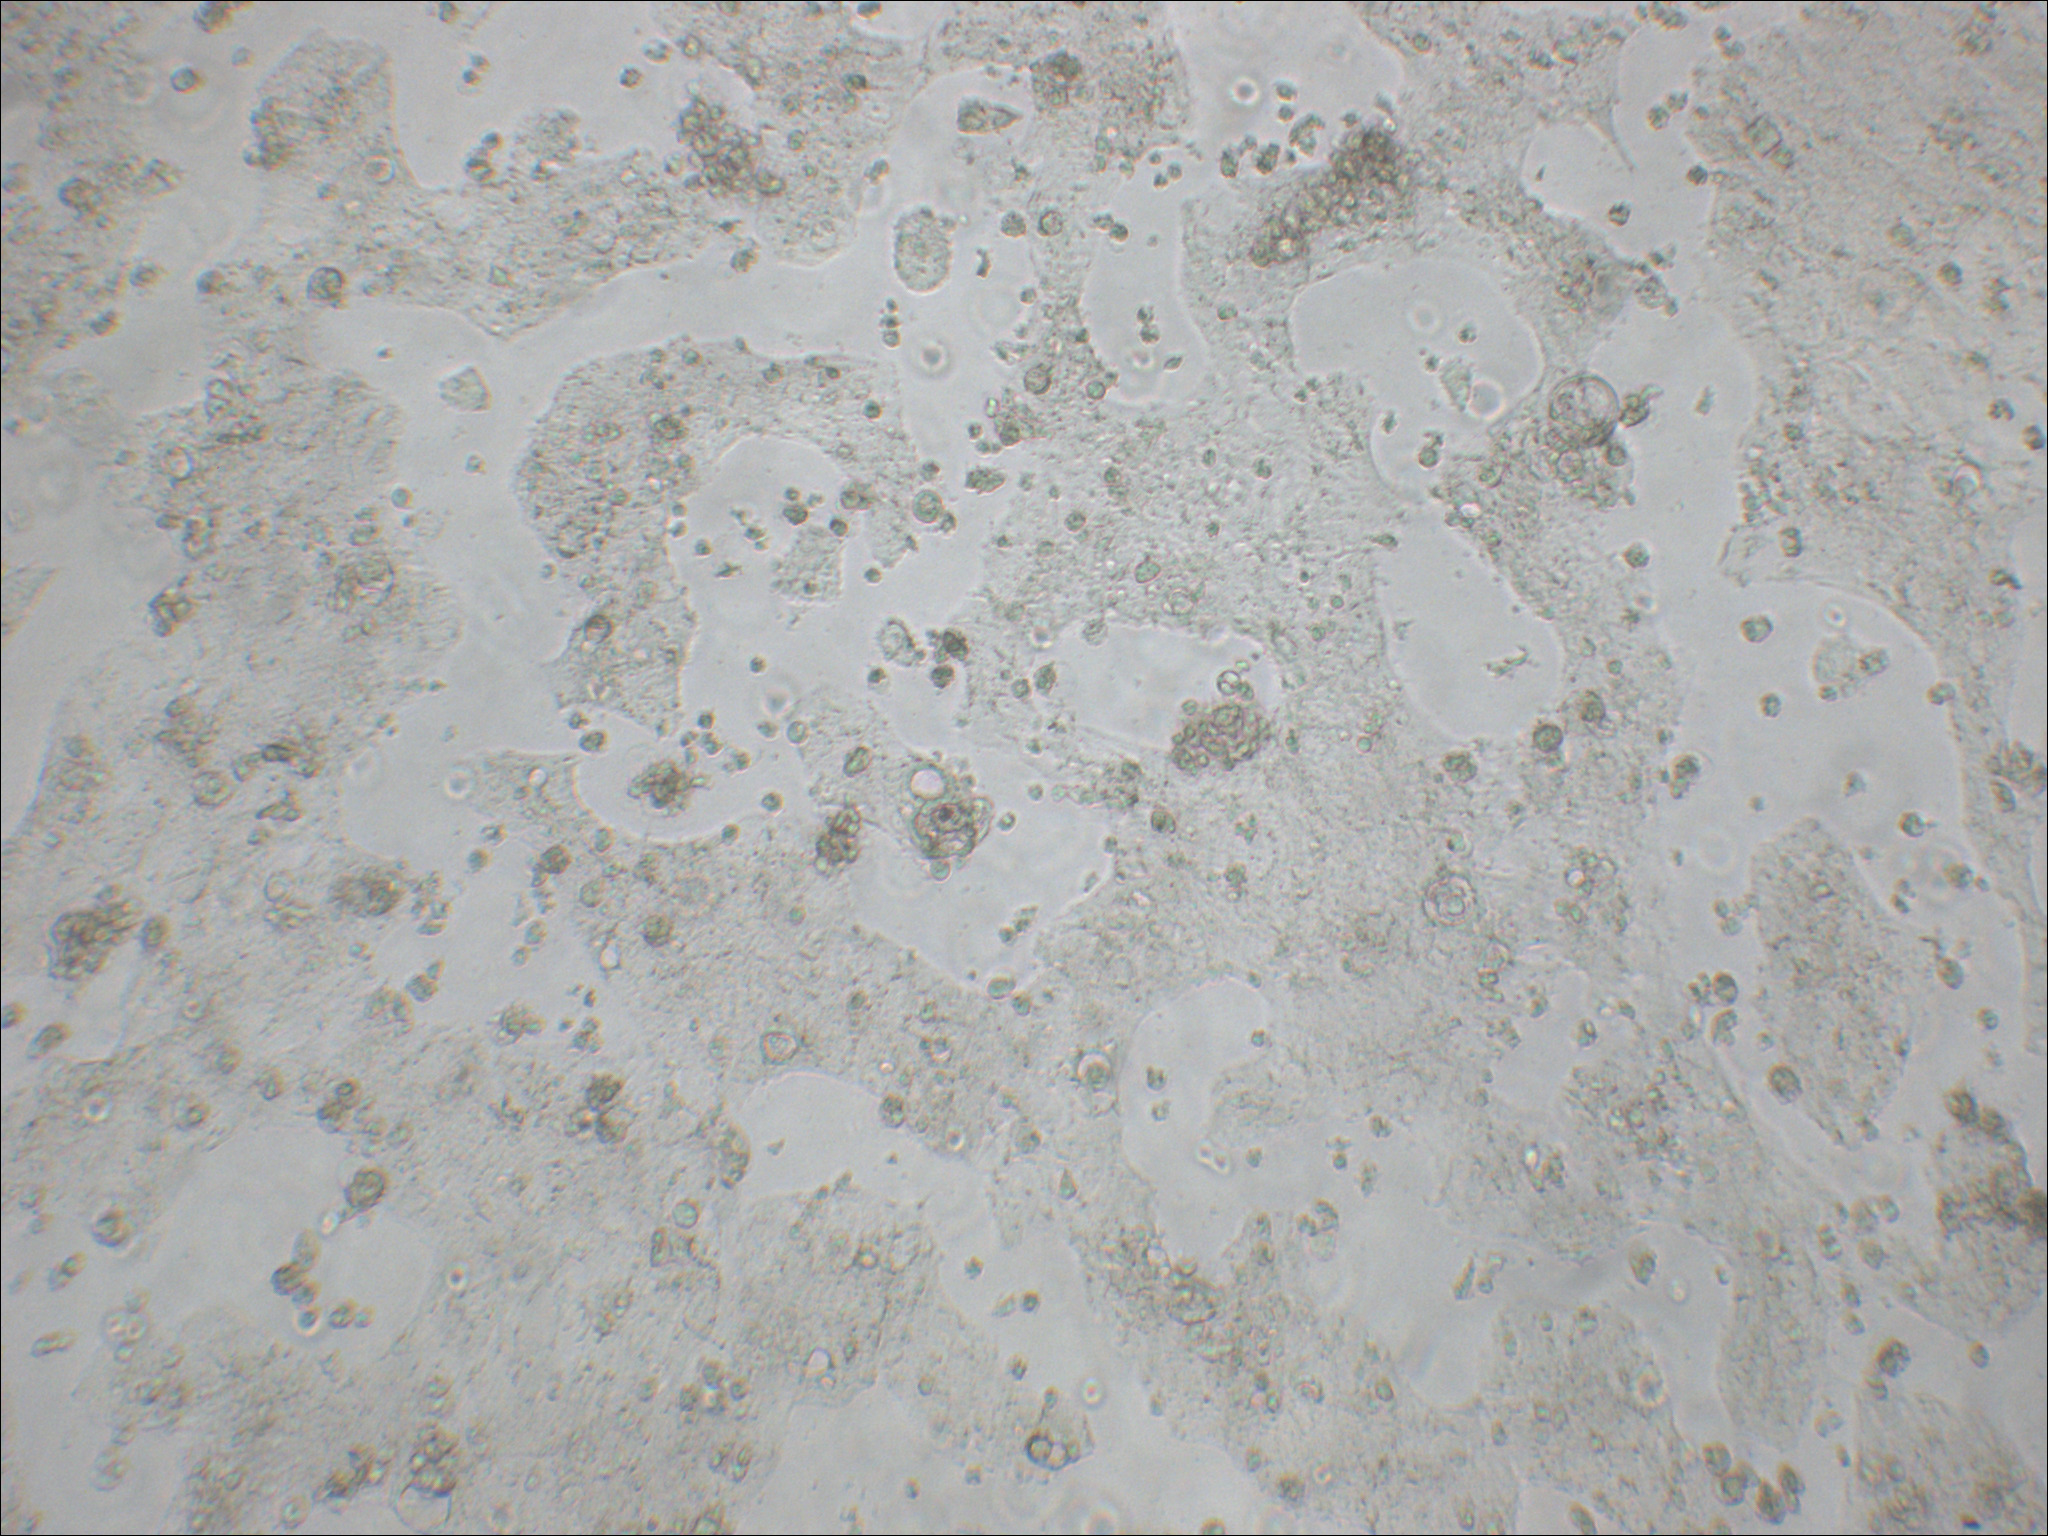

特征特性 此细胞株分离自一个原发性结肠癌。当细胞长满时,表现出典型的肠细胞分化的特征。Caco-2细胞表达维生素A酸结合蛋白I和视黄醇结合蛋白II,角蛋白阳性。

形态特征 上皮细胞样

生长特征 贴壁